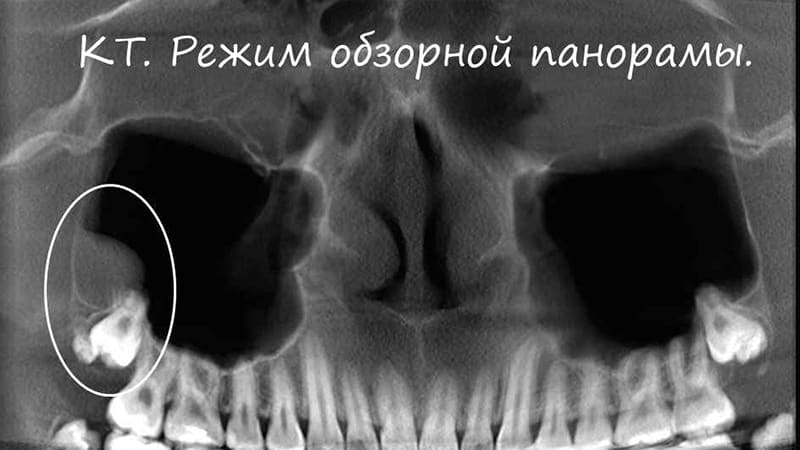

Сложное удаление зубов мудрости может иметь некоторые последствия, хотя риск минимален. Эти последствия могут быть вызваны различными факторами, такими как нарушение направления роста, деформация и изгиб корней, полностью или частично ратинированный зуб, а также уход корней в гайморову пазуху. Неприятные последствия обычно связаны с ошибками врача. Давайте рассмотрим наиболее распространенные ошибки при удалении зуба мудрости, их последствия и возможные решения проблемы. Например, случайное повреждение тканей полости рта или соседнего моляра является довольно распространенной ошибкой неопытных врачей. В таких случаях можно попытаться восстановить поврежденный зуб, если повреждение незначительное. Однако, если коронка полностью разрушена, придется удалить моляр. Еще одним возможным осложнением является повреждение тканей десен из-за короткой области коронки зуба мудрости, когда инструменты могут травмировать мягкие ткани. В таких случаях может потребоваться наложение швов для остановки кровотечения. Перелом альвеолярного отростка также может быть последствием слишком сильного захвата зуба при его удалении. Это может привести к разрушению костной ткани и длительному процессу заживления лунки. Редким, но возможным осложнением является случайный вывих челюсти во время хирургического вмешательства, обычно вызванный неопытностью врача и чрезмерными физическими усилиями. Еще одной проблемой может стать проникновение инструмента или обломков корня зуба в гайморову пазуху, что часто происходит из-за особенностей строения моляров и расположения их корней. Все эти проблемы могут быть решены и скорректированы после удаления зуба мудрости, хотя могут вызвать некоторые временные неудобства для пациента. Важно помнить, что даже после успешного удаления зуба мудрости без осложнений могут возникнуть другие неприятные последствия.